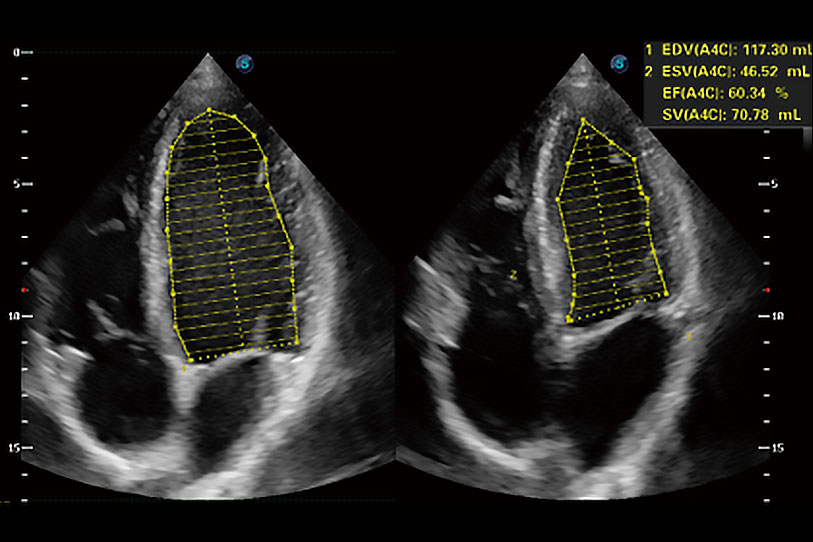

能夠基于左心室壁追蹤和辛普森法,自動計(jì)算射血分?jǐn)?shù),支持多個可移動點(diǎn)描跡,與手動測量相比,極大節(jié)省了動物醫(yī)生的時(shí)間和精力。